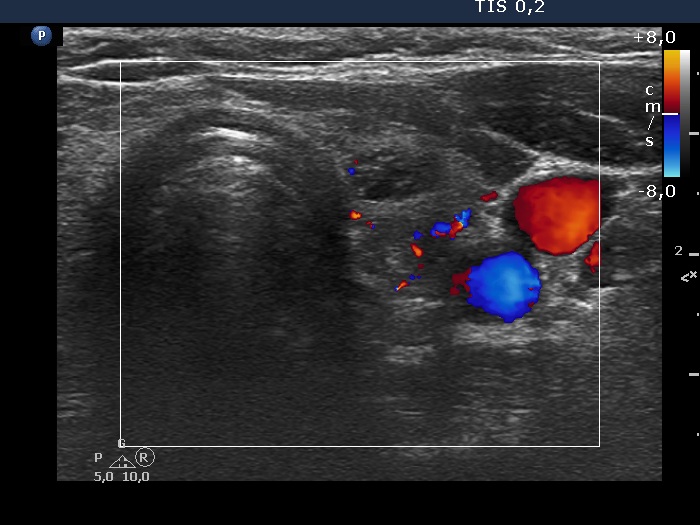

Discrete lesion or nodule in Hashimoto's thyroiditis - case 33 (1650) (ultrasonographic picture 11)

Left lobe, transverse scan, color Doppler mode. The vascularization is not specific.